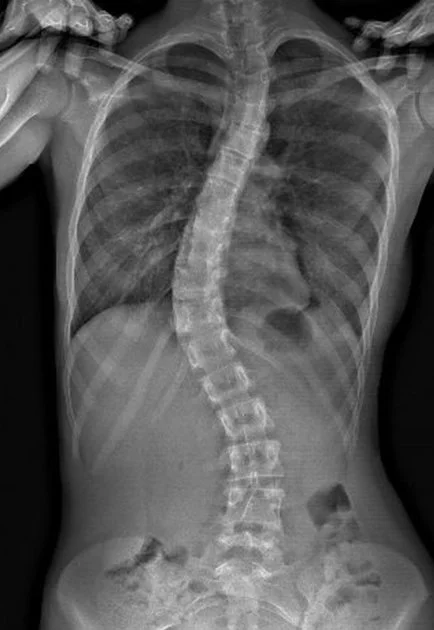

Spine Imaging

Detailed 2D/3D scans for evaluating spinal alignment and conditions, including scoliosis, kyphosis, postural imbalances, degenerative disc changes, spinal misalignment, chronic back or neck pain and sports or posture-related spinal issues.